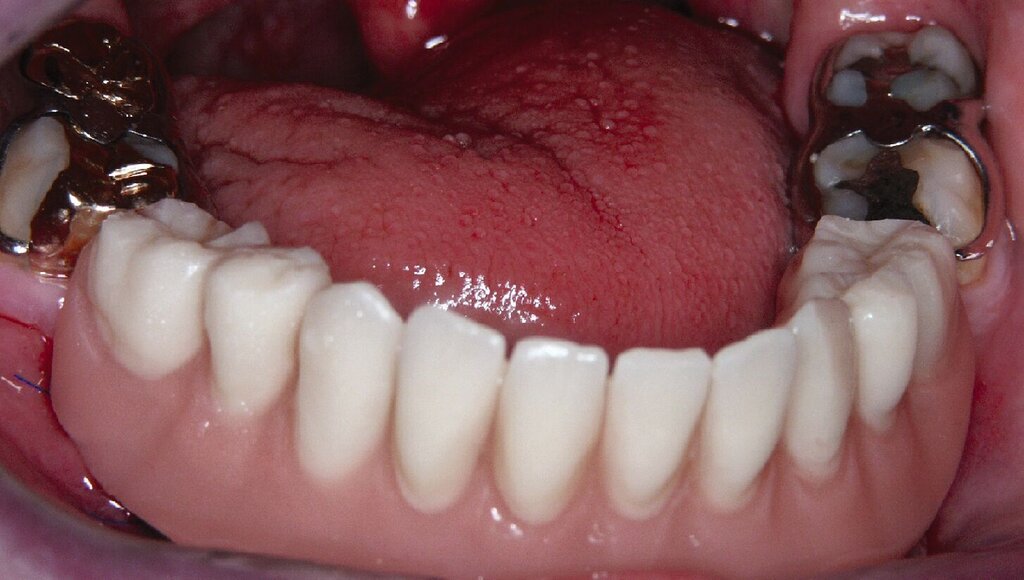

Eine präoperativ vorbereitete Interimsprothese, die über zwei gegossene Bonwill-Klammern sowie das verbliebene Implantat in regio 35 stabil abgestützt war, diente gleichzeitig als Verbandsplatte (Abb. 1f). Auf eine Glättung scharfer Knochenkanten oder die Nivellierung der Kieferkämme wurde verzichtet, um einen iatrogenen Knochenverlust zu vermeiden und das regenerative Potenzial des verbliebenen Knochens zu nutzen (Abb. 1g). Bereits bei der röntgenologischen Kontrolle nach drei Monaten war eine deutliche Zunahme des Knochens im Bereich der alten Implantatpositionen zu erkennen (Abb. 1h). Eine Nachimplantation von vier Implantaten in den Positionen 32, 34, 42 und 44 erfolgte neun Monate nach der Explantation und einer vorangegangenen Verbesserung der Weichgewebsbedeckung durch multiple freie Schleimhautransplantate vom harten Gaumen. Die knöcherne Regeneration unter der gut abgestützten Modellgussprothese verlief so günstig, dass sich der vertikale Höhenverlust des Alveolarkamms im Bereich der gescheiterten Implantate auf circa 2 mm begrenzen ließ. Das zur Entlastung der Kieferkämme und der einheilenden Implantate außerordentlich hilfreiche Implantat in regio 35 wurde erst nach dem Einheilen der nachgesetzten Implantate entfernt. Nach der Einheilzeit der Implantate von weiteren drei Monaten wurde eine kombiniert Zahn/Implantat-gestützte Teleskopprothese mit intraoral verklebten Galvano-Sekundärkronen eingegliedert (Abb. 1k bis 1m). Inzwischen ist diese, wie eine herausnehmbare Brücke abgestützte UK-Prothese seit zehn Jahren funktionstüchtig ohne Zeichen einer Periimplantitis an den vier Implantaten.